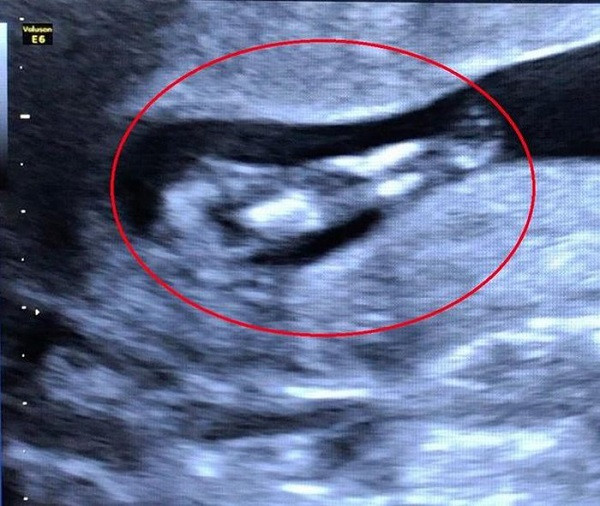

Bệnh nhân 32 tuổi đến thăm khám định kỳ với tuổi thai 11 tuần 5 ngày. Qua kết quả hình ảnh siêu âm cho thấy thai nhi hai chân dính vào nhau giống như đuôi cá, bất thường ở bàng quang và hệ tiết niệu, dây rốn một động mạch.

| Hình ảnh ghi nhận trường hợp thai nhi mắc hội chứng người cá trên siêu âm. Ảnh: BVCC. |